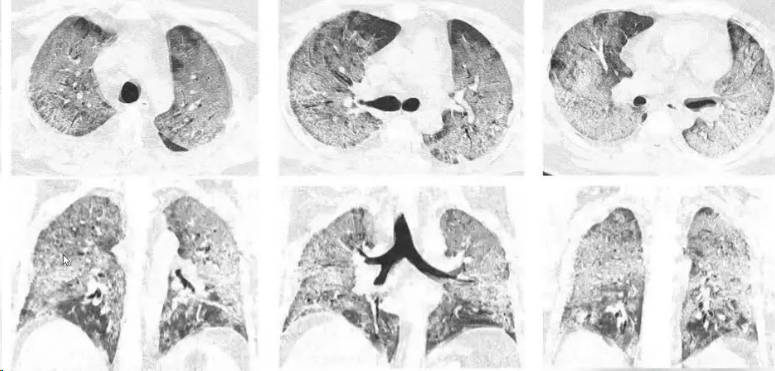

“白肺”并不是一个专业的医学术语,是肺部影像学表现的一个口语化描述,因而并没有一个严格的医学定义。临床上,“白肺”一般指肺部大面积炎症所产生的影像学表现。医务人员之间说白肺,是说患者肺部炎症比较重,只有当肺部双侧病变达到75%以上,才叫白肺。一般达到这个程度会出现会感到呼吸急促、费力,呼吸频率明显加快,即使在安静状态下也会有明显气短。咳嗽比较剧烈,高热、口唇发紫,乏力、肌肉酸痛、食欲不振、精神萎靡等症状。